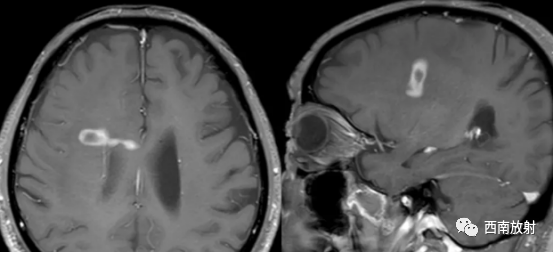

▲病例:脑淋巴瘤。右侧深部脑实质内结节状异常信号,伴周围大面积水肿区,增强扫描呈环状强化。(病例来源东南大学附属中大医院医学影像科)

▲病例:女性,66岁,右肺肺腺癌病癌性淋巴管炎,脑转移瘤,脑内多发类圆形结节影,明显强化。